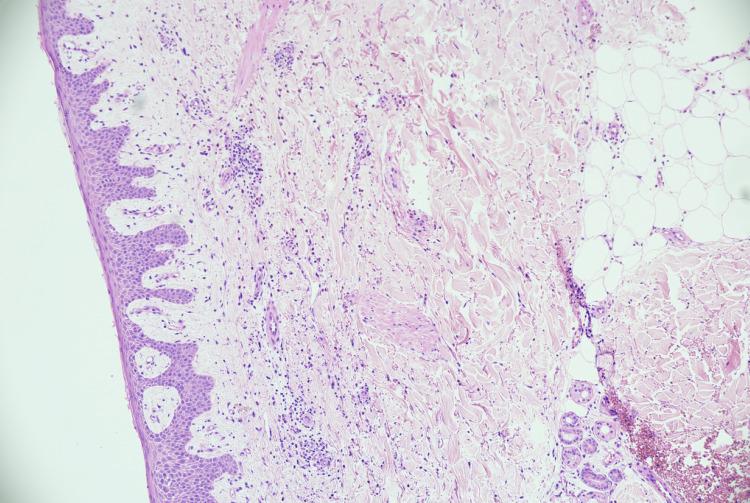

Pemphigus vulgaris is a rare autoimmune disorder, characterised by the development of blistering lesions in the skin and mucosal surfaces throughout the body. It is often misdiagnosed or missed completely in many patients, prolonging their suffering for many years, as it has the ability to mimic an array of other skin diseases. Many studies have concluded that there is a strong association between pemphigus vulgaris and psoriasis, though the exact mechanism is not clearly understood. We present the case of a 77-year-old gentleman on long-term treatment for psoriasis with ultraviolet B phototherapy, steroids, and many other topical treatments who eventually went on to develop pemphigus vulgaris.

寻常型天疱疮是一种罕见的自身免疫性疾病,其特征是在全身皮肤和黏膜表面出现水疱性病变。在许多患者中,它常常被误诊或完全漏诊,从而使他们多年来饱受痛苦,因为它能够模仿一系列其他皮肤病。许多研究得出结论,寻常型天疱疮与银屑病之间存在密切关联,尽管确切机制尚不清楚。我们报告一例77岁男性患者,他长期接受紫外线B光疗、类固醇及许多其他局部治疗来治疗银屑病,最终发展为寻常型天疱疮。